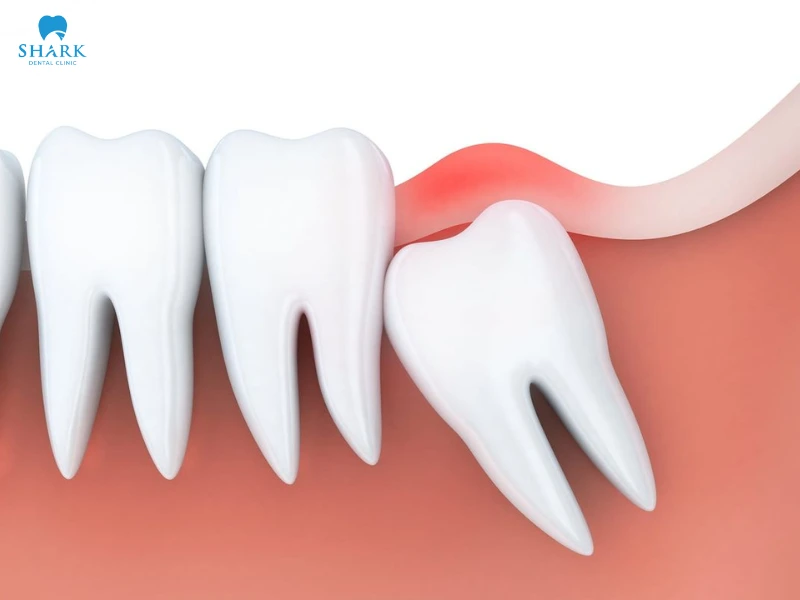

Vì răng khôn mọc ở vị trí cuối trên cung hàm, không đủ chỗ để chen lấn khi các răng kế cận đã mọc hoàn thiện. Do đó, răng mọc sẽ bị mấp mé phần lợi, cọ sát với nướu và dẫn đến hiện tượng răng khôn bị lợi trùm.

Răng khôn mọc lệch

Một số những trường hợp lợi trùm răng khôn là do răng không thể mọc đúng hướng. Răng khôn mọc lệch, đâm vào răng số 7 hoặc răng khôn mọc ngầm.

Từ đó phần lợi sẽ sưng tấy, đau nhức do vi khuẩn dễ dàng tích tụ. Lợi sẽ có dấu hiệu nhiễm trùng và xuất hiện tình trạng lợi trùm lên răng khôn.